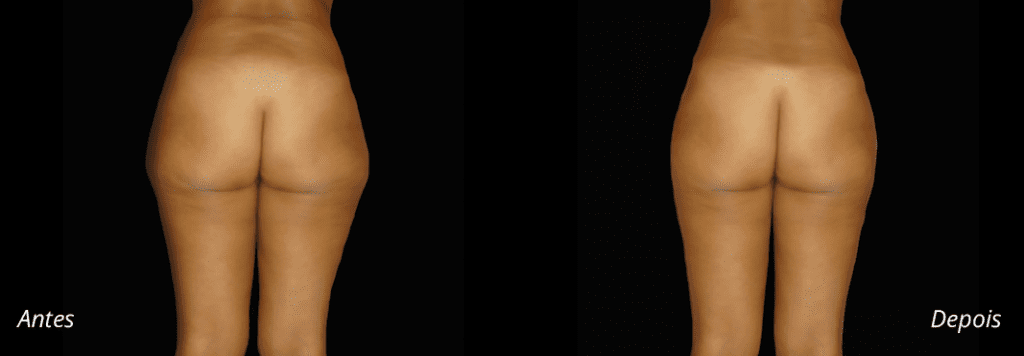

Imagens antes e depois